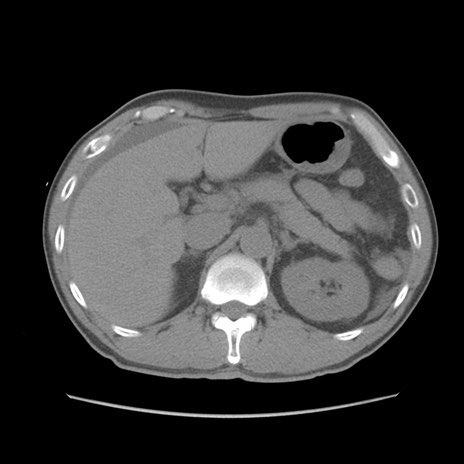

症例56 CT(横断像)

脂肪ウインドウ